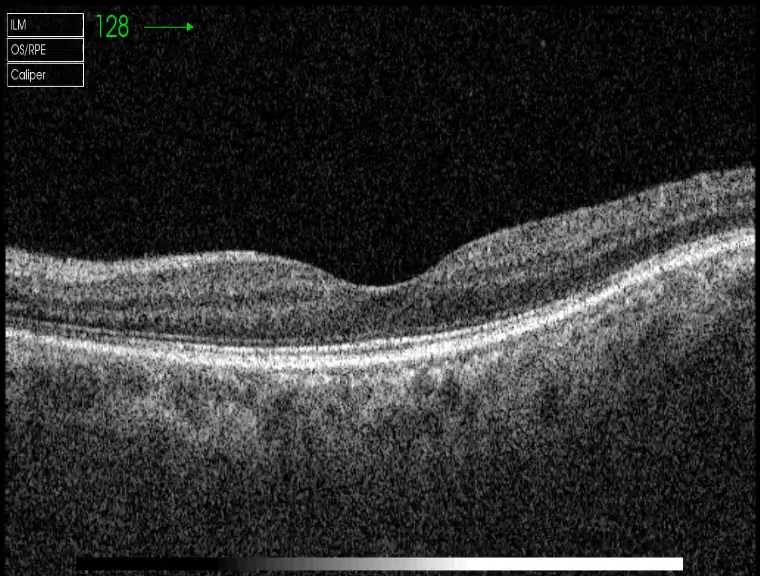

黄斑OCT:右眼明显脉络膜水肿增厚并可见RPE明显波浪样起伏,后极椭圆体带模糊消失,并 可见局限浆液性视网膜神经感觉层浅脱离,未见视网膜水肿增厚,未见明显黄斑区视网膜表 面新生血管样高反射信号,OCTA也未见新生血管信号;左眼视网膜平坦无起伏,网膜、脉络 膜大致可,黄斑区未见视网膜神经感觉层浅脱离,未见黄斑区网膜水肿,未见明确视网膜新 生血管样病灶。OCTA双眼未见明显脉络膜新生血管样病灶,但双眼可见明显后极广泛多发脉络膜毛细血管低信号斑点。 双眼B超:右眼球壁厚度明显增厚,后极球壁厚度约3mm,未见T形征,左眼后极B超未见明显 异常。

左OCT